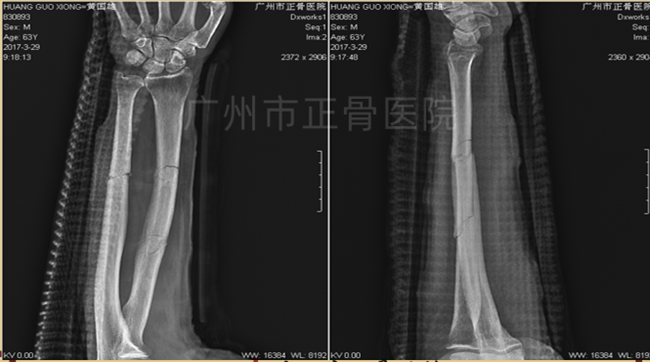

治疗:运用黄氏正骨手法复位骨折并以小夹板外固定,复查X线片提示骨折端位置良好。3天后复查X线见尺骨移位,调整后加石膏托固定,复查X线提示骨折端位线较前改善。1周后复查X线提示骨折稳定。维持石膏、夹板固定,继续复查换药,指导患者适当功能锻炼。6周后,可见轻微骨痂生长。2个月后骨折线部分模糊,2个半月后复查X线提示骨痂生长增多,骨折端稳定,拆除外固定,指导患者循序渐进进行功能康复锻炼。3个月后,患者功能恢复正常。1年后复查X线片,提示骨性愈合。

▲1周后,骨折端稳定

▲4周后,骨折端稳定,少量骨痂生长